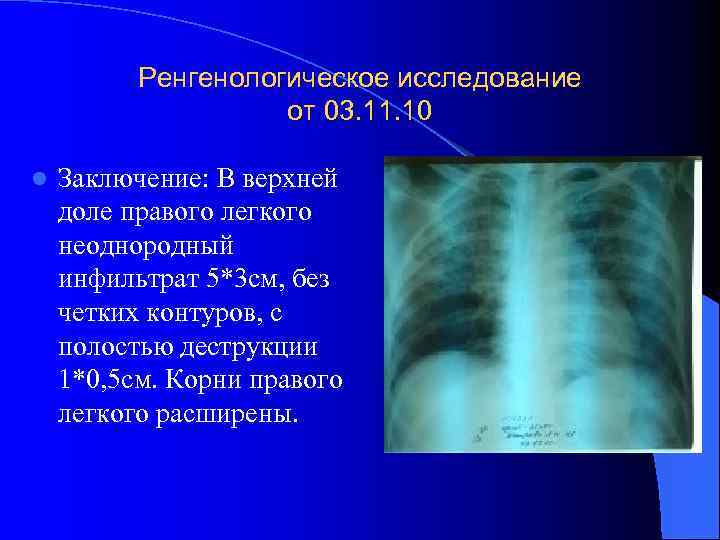

Симптомы и лечение инфильтративного туберкулеза легких

Раздел: Снимки-откровения